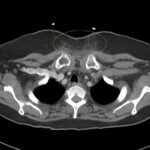

Retropharyngeal abscess (RPA) is an uncommon yet potentially life-threatening condition that is more often seen in young children and may be misdiagnosed in adults presenting with atypical features.1 Retropharyngeal abscess results from spread of antecedent upper respiratory tract infection or traumatic inoculation via foreign body ingestion or medical instrumentation. Clinically, RPA may present with fever, pharyngitis, neck pain, and dysphagia. Diagnosis is often confirmed with imaging studies. We present a case of a 66-year-old female with asthma, hypertension, and gastroesophageal reflux disease (GERD) who presented to the emergency department (ED) for evaluation of neck fullness, shoulder pain, dysphagia, and abdominal pain starting less than 24 hours prior to presentation. Computed tomography (CT) revealed a prevertebral/retropharyngeal fluid collection from the odontoid tip to the C4 vertebral body measuring 5.4 x 1.0 x 3.3 centimeters (cm) in size with associated edema at the left neck base extending into the upper chest, suggestive of retropharyngeal abscess. The patient received intravenous (IV) vancomycin and piperacillin/tazobactam and was transferred to a higher level of care for otolaryngologist evaluation. The patient remained stable without airway compromise while in our department. This case underscores challenges in diagnosing atypical presentations of RPA in adults, emphasizing timely recognition to prevent complications.